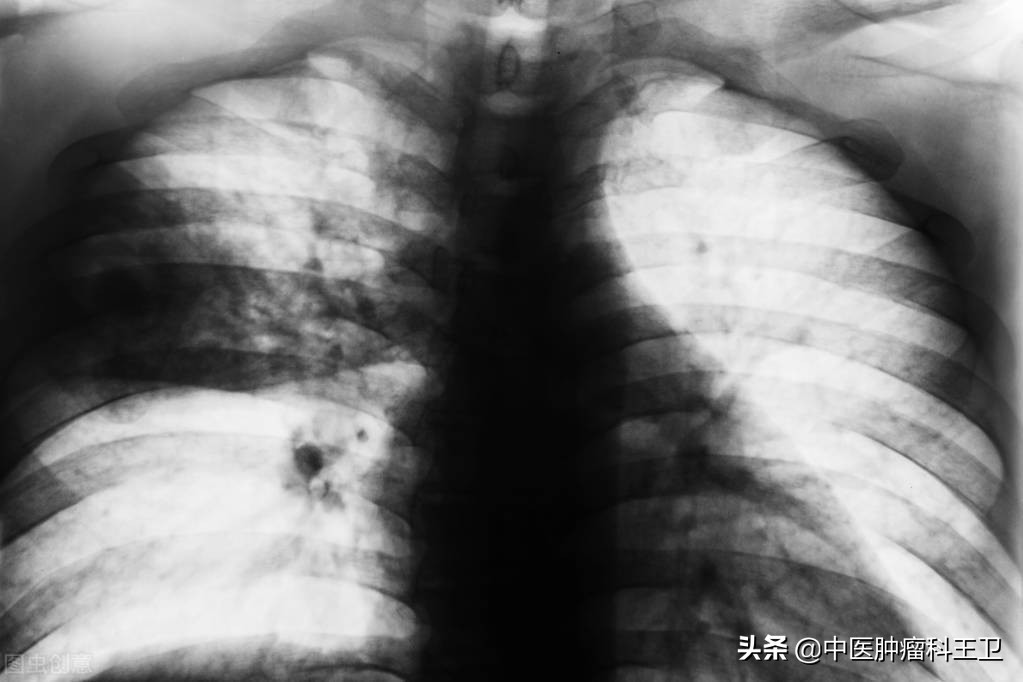

咱们以一位患者为例,65岁,女性,通过常规体检胸部CT,查出肺部结节,病灶1.6cm,穿刺活检提示为腺癌,中-低分化。因为病灶不算大,而且患者年纪也大,一开始考虑不做手术,但是当做了脑部磁共振检查,发现已经脑转移了。这个结果令患者全家都无法接受深受打击,后来又通过一系列的检查,最终决定用化疗来治病。但是,在化疗治疗中,患者身体每况愈下,经常寒颤高热,恶心呕吐,就快要承受不了化疗带来的副作用了,这才想着能不能用中药来减轻痛苦。